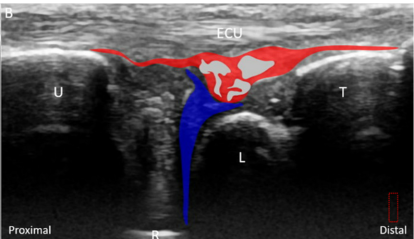

@ DOI: 10.3390/jcm8101540

반월 연골 유사체 아래에는

보라색으로 표시한

월상 삼각 인대(Luno-Triquertral ligament)

가 보입니다.

그 아래에는 녹색으로 표시한

가장 중요한 구조물이죠.

바로 '삼각섬유연골' 이라는(Triangular fibrocartilage, TFC)

관절 디스크(Articular disc)가

요골에 붙어있습니다.

MRI상 삼각섬유연골 파열로

진단 받으신 분들은

표준 경혈 초음파와 달리이렇게까맣게 손상된 틈이 보이는데요.

제가 1억이 넘는 GE초음파 최상위 기종

LOGIQ FORTIS를 쓰고 있는데

사람에 따라서

요골 부착부나 척골 부착부쪽은

안 보일 때가 있습니다.